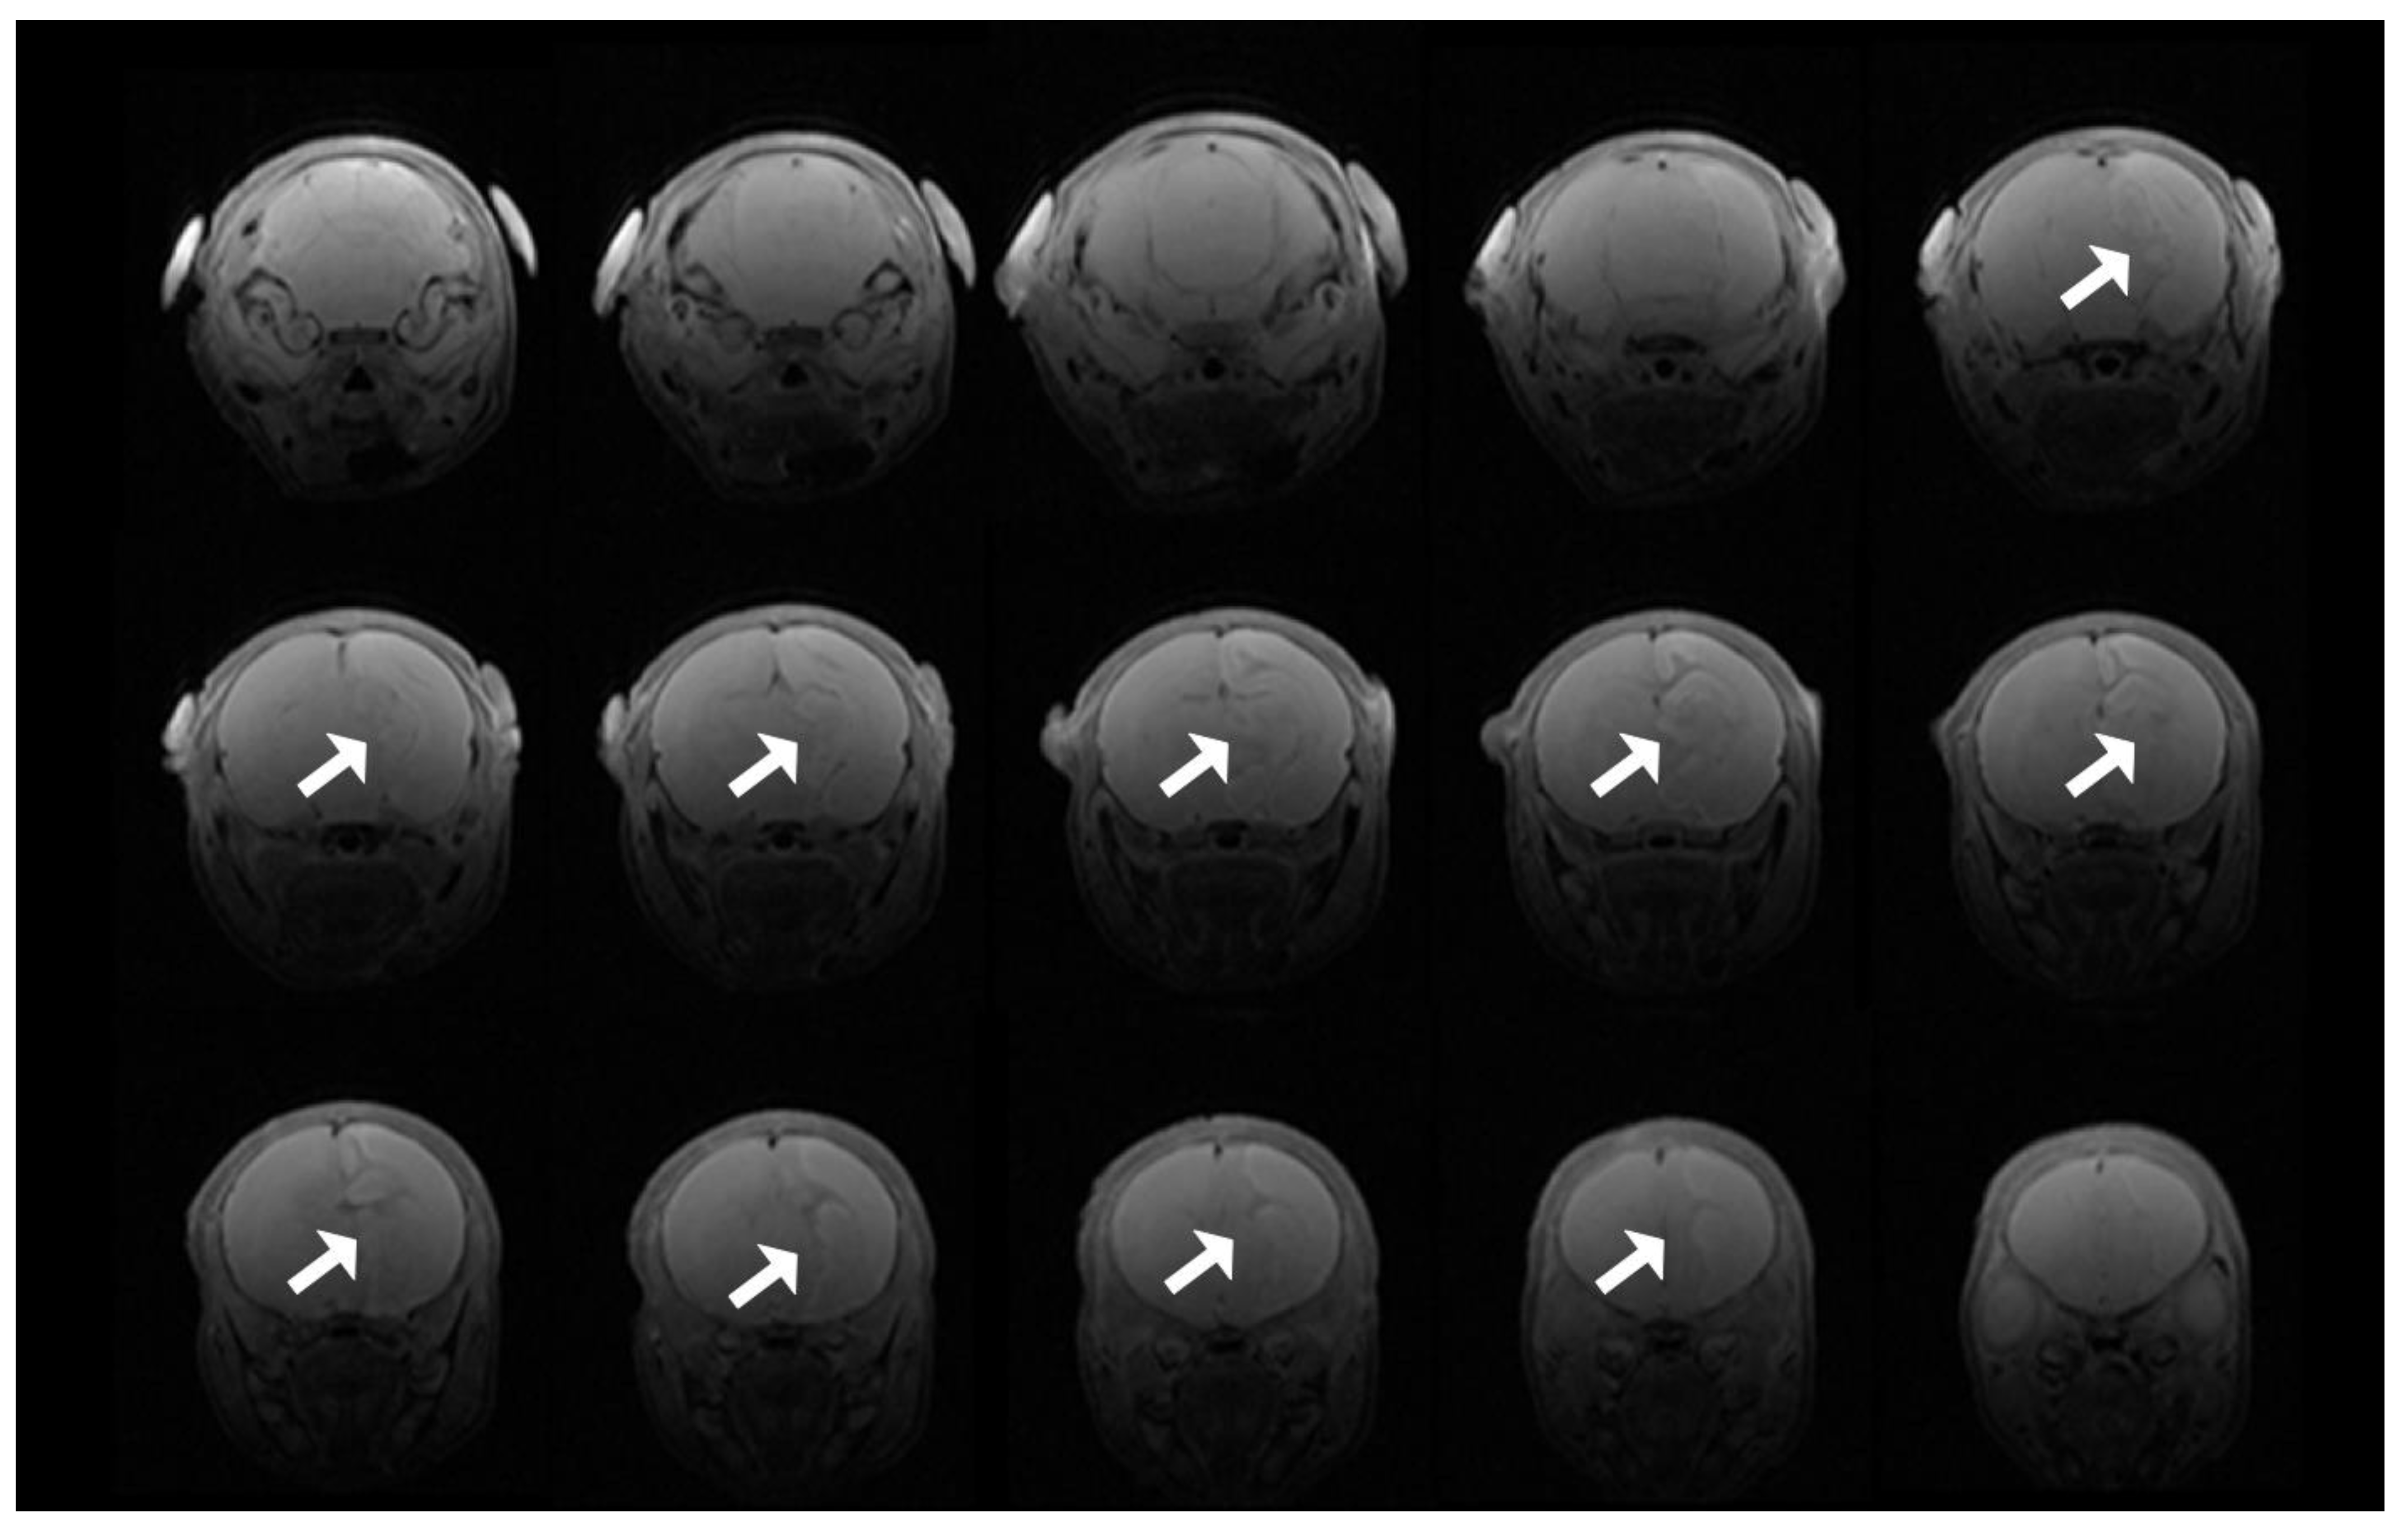

3.8. T2 Evidence of Infarcts